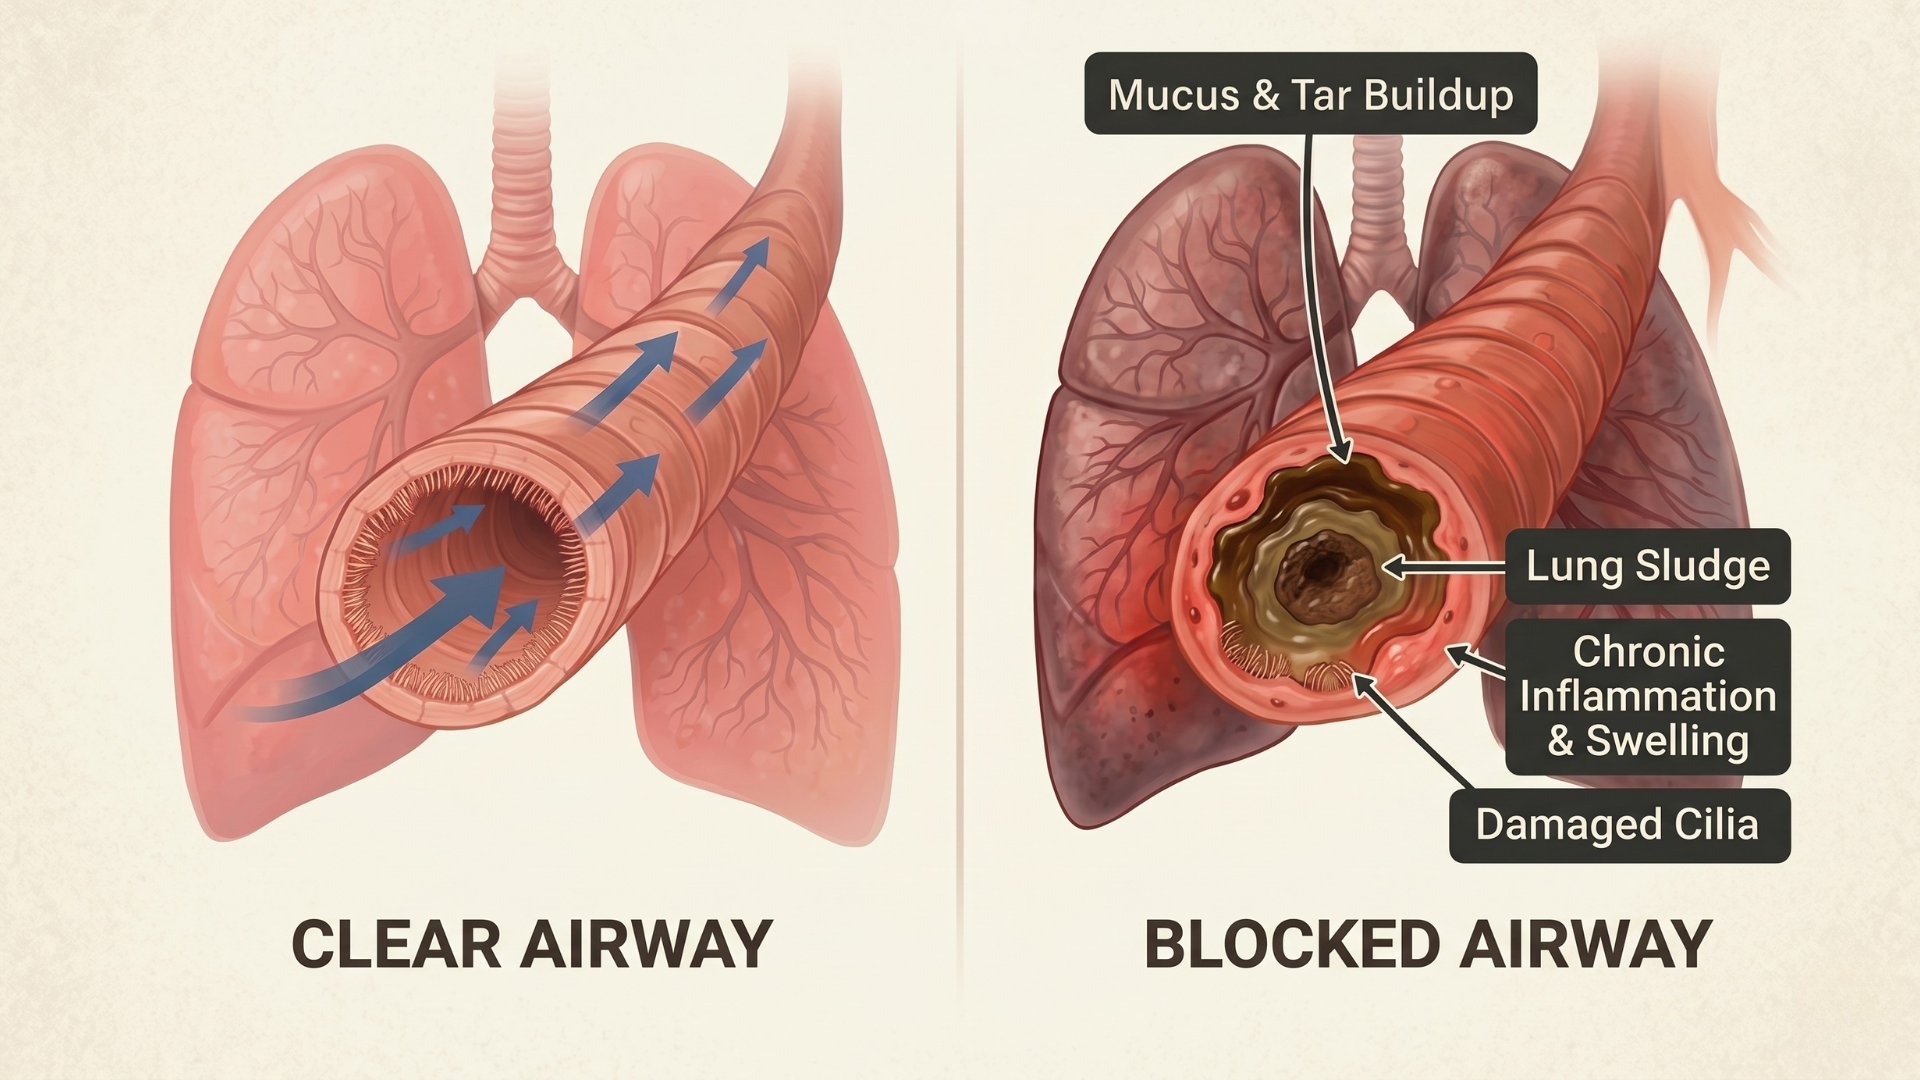

Your lungs have a natural clearing system — tiny hair-like cilia and mucus membranes that continuously sweep irritants out of your airways.

When it is working properly, you do not even know it exists:

Mucus moves through in hours

Chest stays clear and comfortable

Body feels light, energized, and normal

The cilia slow down and become coated

Mucus thickens and backs up in your airways

Inflammation and congestion skyrocket

And it builds up. Hour after hour. Day after day.

That mucus that should clear in hours? It is sitting in your lungs for 8, 10, 12 hours. Thickening. Triggering inflammation. Creating that heavy, congested feeling — and aging your airways faster than anything else.

The morning cough that should be gone by noon? It is still there at dinner. When you are trying to fall asleep. The next morning when you wake up congested again.

The cilia slow down and become coated

Mucus thickens and backs up in your airways

Inflammation and congestion skyrocket

Your lung age accelerates ahead of your real age

YOUR LUNGS AREN'T FAILING...

THEY'RE CLOGGED